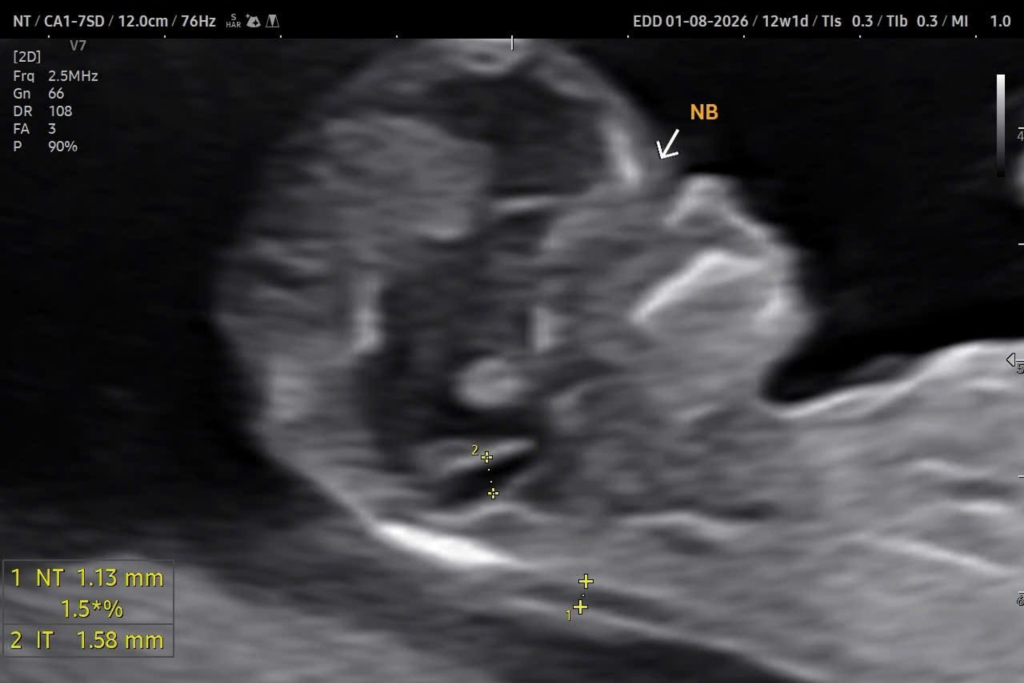

Bất sản xương mũi là tình trạng không thấy hình ảnh xương mũi trên mặt cắt dọc giữa khuôn mặt thai nhi khi siêu âm. Ở thai bình thường, xương mũi thai nhi xuất hiện như một đường tăng âm sáng song song với da. Khi không thấy đường tăng âm này, bác sĩ có thể ghi nhận bất sản hoặc không thấy xương mũi.

Tình trạng này thường được phát hiện ở siêu âm 12 tuần, giai đoạn sàng lọc bất thường nhiễm sắc thể.

Phân biệt bất sản thật sự và không quan sát thấy do kỹ thuật

Không phải mọi trường hợp ghi nhận không thấy xương mũi đều là bất sản thật sự.

Việc đánh giá xương mũi phụ thuộc vào:

Mặt cắt dọc giữa chuẩn.

Góc đầu dò vuông góc với xương mũi.

Kinh nghiệm của người thực hiện siêu âm thai.

Nếu mặt cắt không chuẩn, hình ảnh xương mũi có thể bị bỏ sót.

Vì vậy, khi nhận kết quả không thấy xương mũi, nên siêu âm kiểm tra lại tại cơ sở có kinh nghiệm.